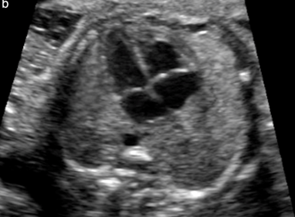

What view is this?

4 chamber view

Normal 4 chamber view